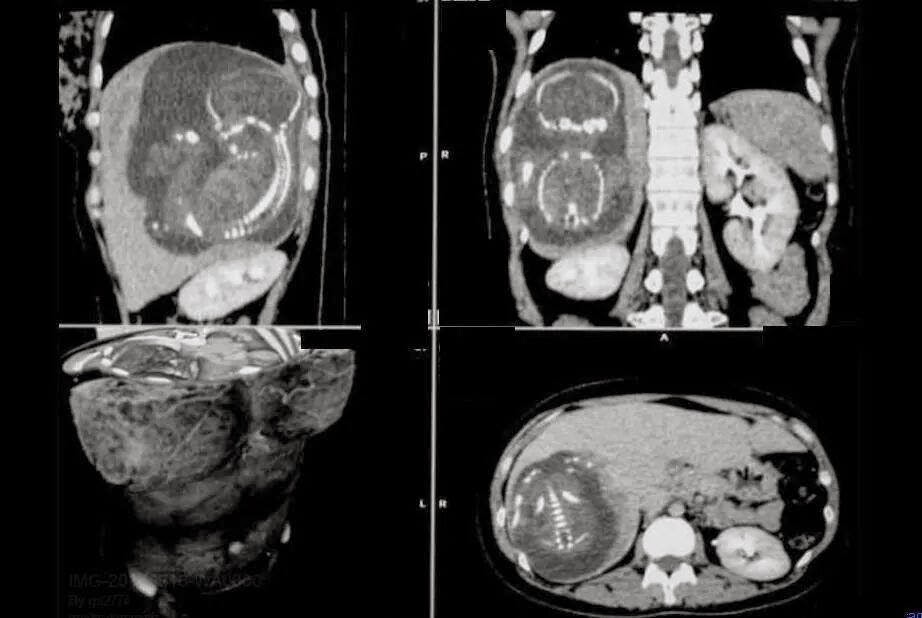

Imaging Anatomy SMS Miracle baby 'grew in liver' Problems With Liver In Babies congenital liver defects are liver disorders that are present at birth. understanding childhood liver failure. acute liver failure newborns is an acute liver failure in the first 28 days of life. there are many different childhood liver conditions and problems. there are a variety of different diseases of the liver that can affect your child.. Problems With Liver In Babies.